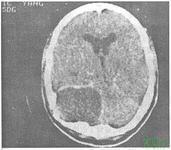

颅内胆脂瘤

颅内胆脂瘤是起源于异位胚胎残余组织的先天性良性肿瘤,可为多发,无明显性别差异,任何年龄均可发病,高峰年龄均在40岁。

颅内胆脂瘤的好发部位:好发于脑室或脑池,可延脑室脑池蔓延。最常见的位于小脑桥脑角、鞍旁,也见于第四脑室,侧脑室、大脑、小脑和脑干。发生在颅骨桥障和脊柱者约占25%。